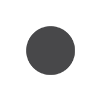

Λίγο αργότερα ένας αστυνομικός ακούγεται να λέει: «Κατάπιε κάτι». Ο 32χρονος ληστής συνελήφθη και μεταφέρθηκε στο νοσοκομείο, όπου αρνήθηκε να υποβληθεί την ακτινογραφία. Στη φυλακή υποχρεώθηκε να κάνει ακτινογραφία και τελικά εντοπίστηκαν ξένα αντικείμενα στο στομάχι του.

«Θα κατηγορηθώ για αυτό που βρίσκεται στο στομάχι μου;», φέρεται να ρώτησε ο ληστής. Αμέσως μετά επέστρεψε στο νοσοκομείο αλλά αρνήθηκε να πάρει καθαρκτικό με την αιτιολογία ότι είναι μουσουλμάνος και έτρωγε μόνο μετά τη δύση του ηλίου και πριν την ανατολή λόγω του Ραμαζανιού.

Τελικά μετά από εβδομάδες οι αρχές παρακολουθούσαν τις κενώσεις του εντέρου του ληστή και κατάφεραν να πάρουν τα διαμάντια.